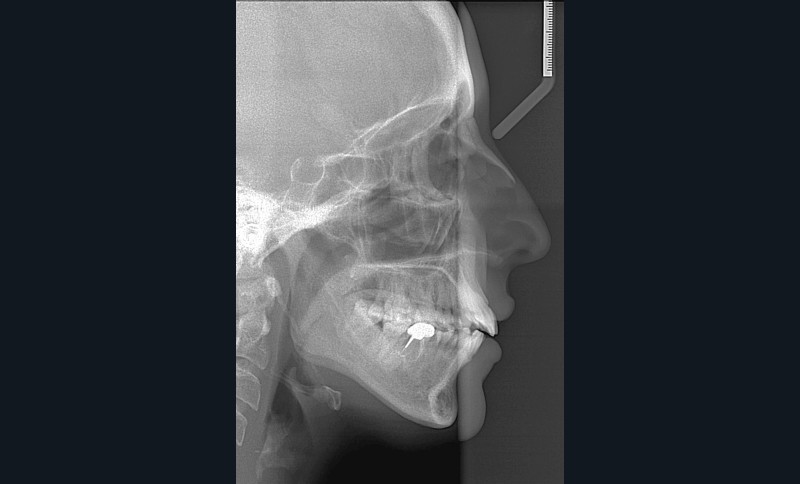

C’est précisément le cas de cette patiente de 33 ans qui présente une classe II squelettique par rétrognathie mandibulaire sur un schéma vertical hyperdivergent associée à une classe II/1 dentaire avec DDA par excès et biproalvéolie. Son profil est convexe, cis-frontal et, sur le plan fonctionnel, on peut observer une dysfonction linguale et une incompétence labiale au repos. Il en résulte une contracture des muscles de la sphère péri-orale lèvres jointes. La formule dentaire n’est pas complète puisque les quatre deuxièmes prémolaires ont été extraites lors d’un premier traitement orthodontique et qu’il y a également agénésie des troisièmes molaires 18 et 38 (fig 1 à 11).

Au regard de ces éléments, la décision thérapeutique choisie intègre une prise en charge orthodontique associée à une chirurgie orthognathique d’avancement mandibulaire et à une mentoplastie. L’étape initiale du traitement orthodontique consiste en la levée des compensations dentaires qui se traduit par la correction de la proalvéolie mandi– bulaire dans le but de pouvoir corriger la classe II squelettique et dentaire par avancement chirur- gical de la mandibule. Pour cela, des mini-vis d’ancrage sont positionnées distalement aux secteurs 3 et 4, enfouies à la base des branches mandibulaires avec des chaînettes métalliques émergentes dans la cavité buccale. L’objectif est d’assurer le repositionnement incisif mandibulaire grâce à des modules élastiques.